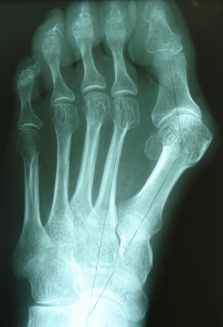

Hallux valgus

Die häufigste Vorfußdeformität ist in der Regel durch einen Spreizfuß verursacht. Mit zunehmender Ausprägung der Deformität kommt es zum Schuhkonflikt und zu einer Kompromittierung der benachbarten Zehen, die von der Großzehe verdrängt wird.

Abhängig von den gemessenen Winkeln im Röntgenbild wird das operative Verfahren gewählt. Je ausgeprägter die Fehlstellung, desto aufwändiger ist das operative Verfahren. Im Folgenden werden verschiedene operative Verfahren anhand von Beispielen vorgestellt, die an unserer Klinik durchgeführt werden.